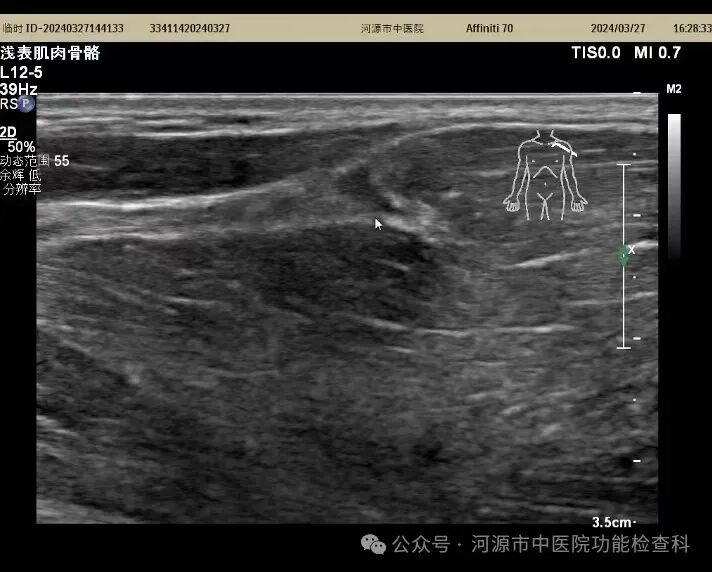

↑肱二头肌长头肌腱断裂